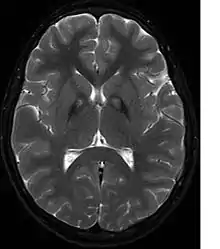

A neurological examination would show evidence of muscle rigidity; weakness; and abnormal postures, movements, and tremors. If other family members are also affected, this may help determine the diagnosis. Genetic tests can confirm an abnormal gene causing the disease. However, this test is not yet widely available. Other movement disorders and diseases must be ruled out. Individuals exhibiting any of the above listed symptoms are often tested using MRI (Magnetic Resonance Imaging) for a number of neuro-related disorders. An MRI usually shows iron deposits in the basal ganglia. Development of diagnostic criteria continues in the hope of further separating PKAN from other forms of neurodegenerative diseases featuring NBIA.

Microscopic features of PKAN include high levels of iron in the globus pallidus and the pars reticulata of substantia nigra, evident as a characteristic rust-brown discoloration[7] in a pattern called the eye-of-the-tiger sign;[8] lipofuscin and neuromelanin concentrated in the iron-accumulating areas; oval, nonnucleated structures representing swollen axons whose cytoplasm swells with vacuoles, referred to as spheroids, axon schollen, or neuroaxonal dystrophy; and Lewy bodies.[7]